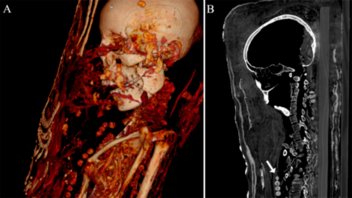

Un equipo de arqueólogos analizó los restos de tres momias egipcias correspondientes al periodo romano tardío -entre finales del siglo III y del siglo IV d.C.-, y descubrió que al menos una de ellas aún conserva el cerebro y otros órganos internos. Estos hallazgos, que aparecen recogidos en la revista Plos One, fueron posibles gracias al uso de nuevos escáneres especializados.

Mediante análisis de tomografía computerizada, los investigadores lograron obtener información sobre el estado de conservación de los cuerpos, la técnica de momificación artificial usada, la edad de los individuos en el momento de la muerte, así como su género, altura y salud.

"Las investigaciones radiológicas anteriores de las momias de los períodos romanos ya revelaron que algunas no mostraban evidencia de extirpación del cerebro y de los intestinos. La identificación del cerebro conservado en el caso de la mujer joven apoya, por lo tanto, esta idea", explicó a IFLScience, el investigador principal del estudio, Stephanie Zesch.

En este sentido, el experto considera el hallazgo como una prueba del cambio de técnicas aplicadas en el tratamiento corporal previo a la momificación, pues la práctica común en Egipto contemplaba la eliminación del cerebro a través de los orificios de la nariz, así como de los órganos internos.

Este nuevo tratamiento fue posible identificarlo solo en la momia joven, pues los cuerpos del hombre y la otra mujer estaban "bastante mal conservados" y no se pudo determinar una técnica específica de momificación artificial.